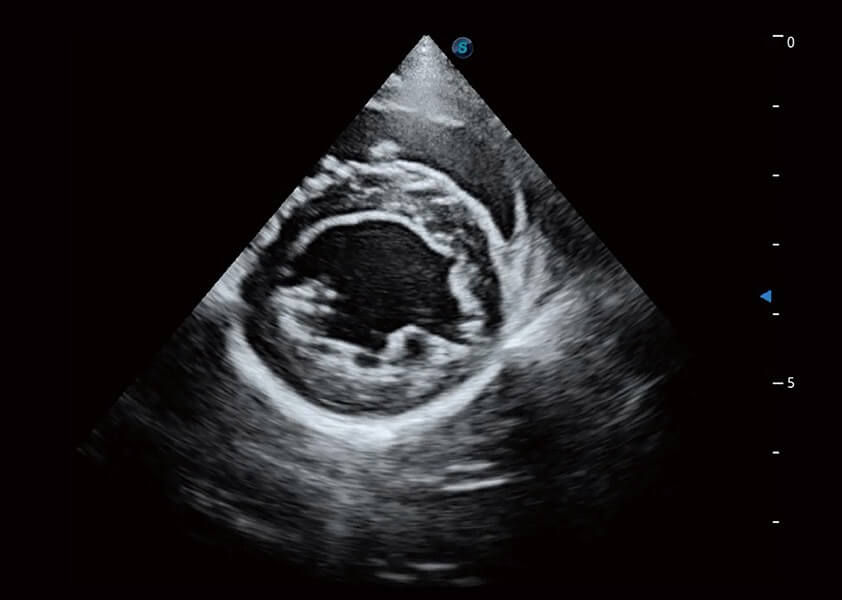

ProPet 60 作为一款高端台式动物超声设备,为动物医生的日常诊断提供了一系列贴合动物临床需求、解决临床实际问题的高级成像功能。凭借全系列高清探头,满足医生对腹部、心脏、生殖、浅表、肌骨等成像的所有需求,切实帮助您提升检查效率,提高诊断信心。

动物是人类最亲密的朋友和最值得信赖的伙伴。银河优越会也一直致力于探索动物专用的超声影像解决方案。 全新推出的ProPet系列,是银河优越会在动物超声影像智能化、专业化、精准化的一次跨越式革新。动物不能用言语来表述自己的不适,通过超声影像,ProPet系列搭建了动物医生与不同物种沟通的“桥梁”,为动物医生注入了“治愈之力”。